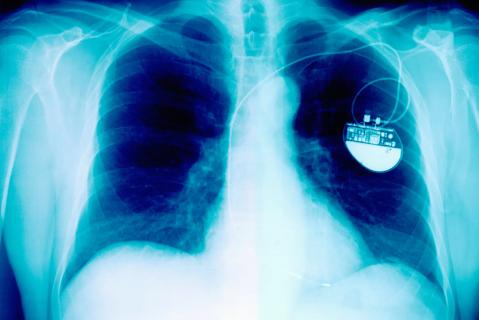

X-Ray Showing Pacemaker

November 21, 2023/London

Cleveland Clinic London Introduces a Comprehensive Cardiac Device Lead-Extraction Programme

First Cases Successfully Performed in UK Private Healthcare